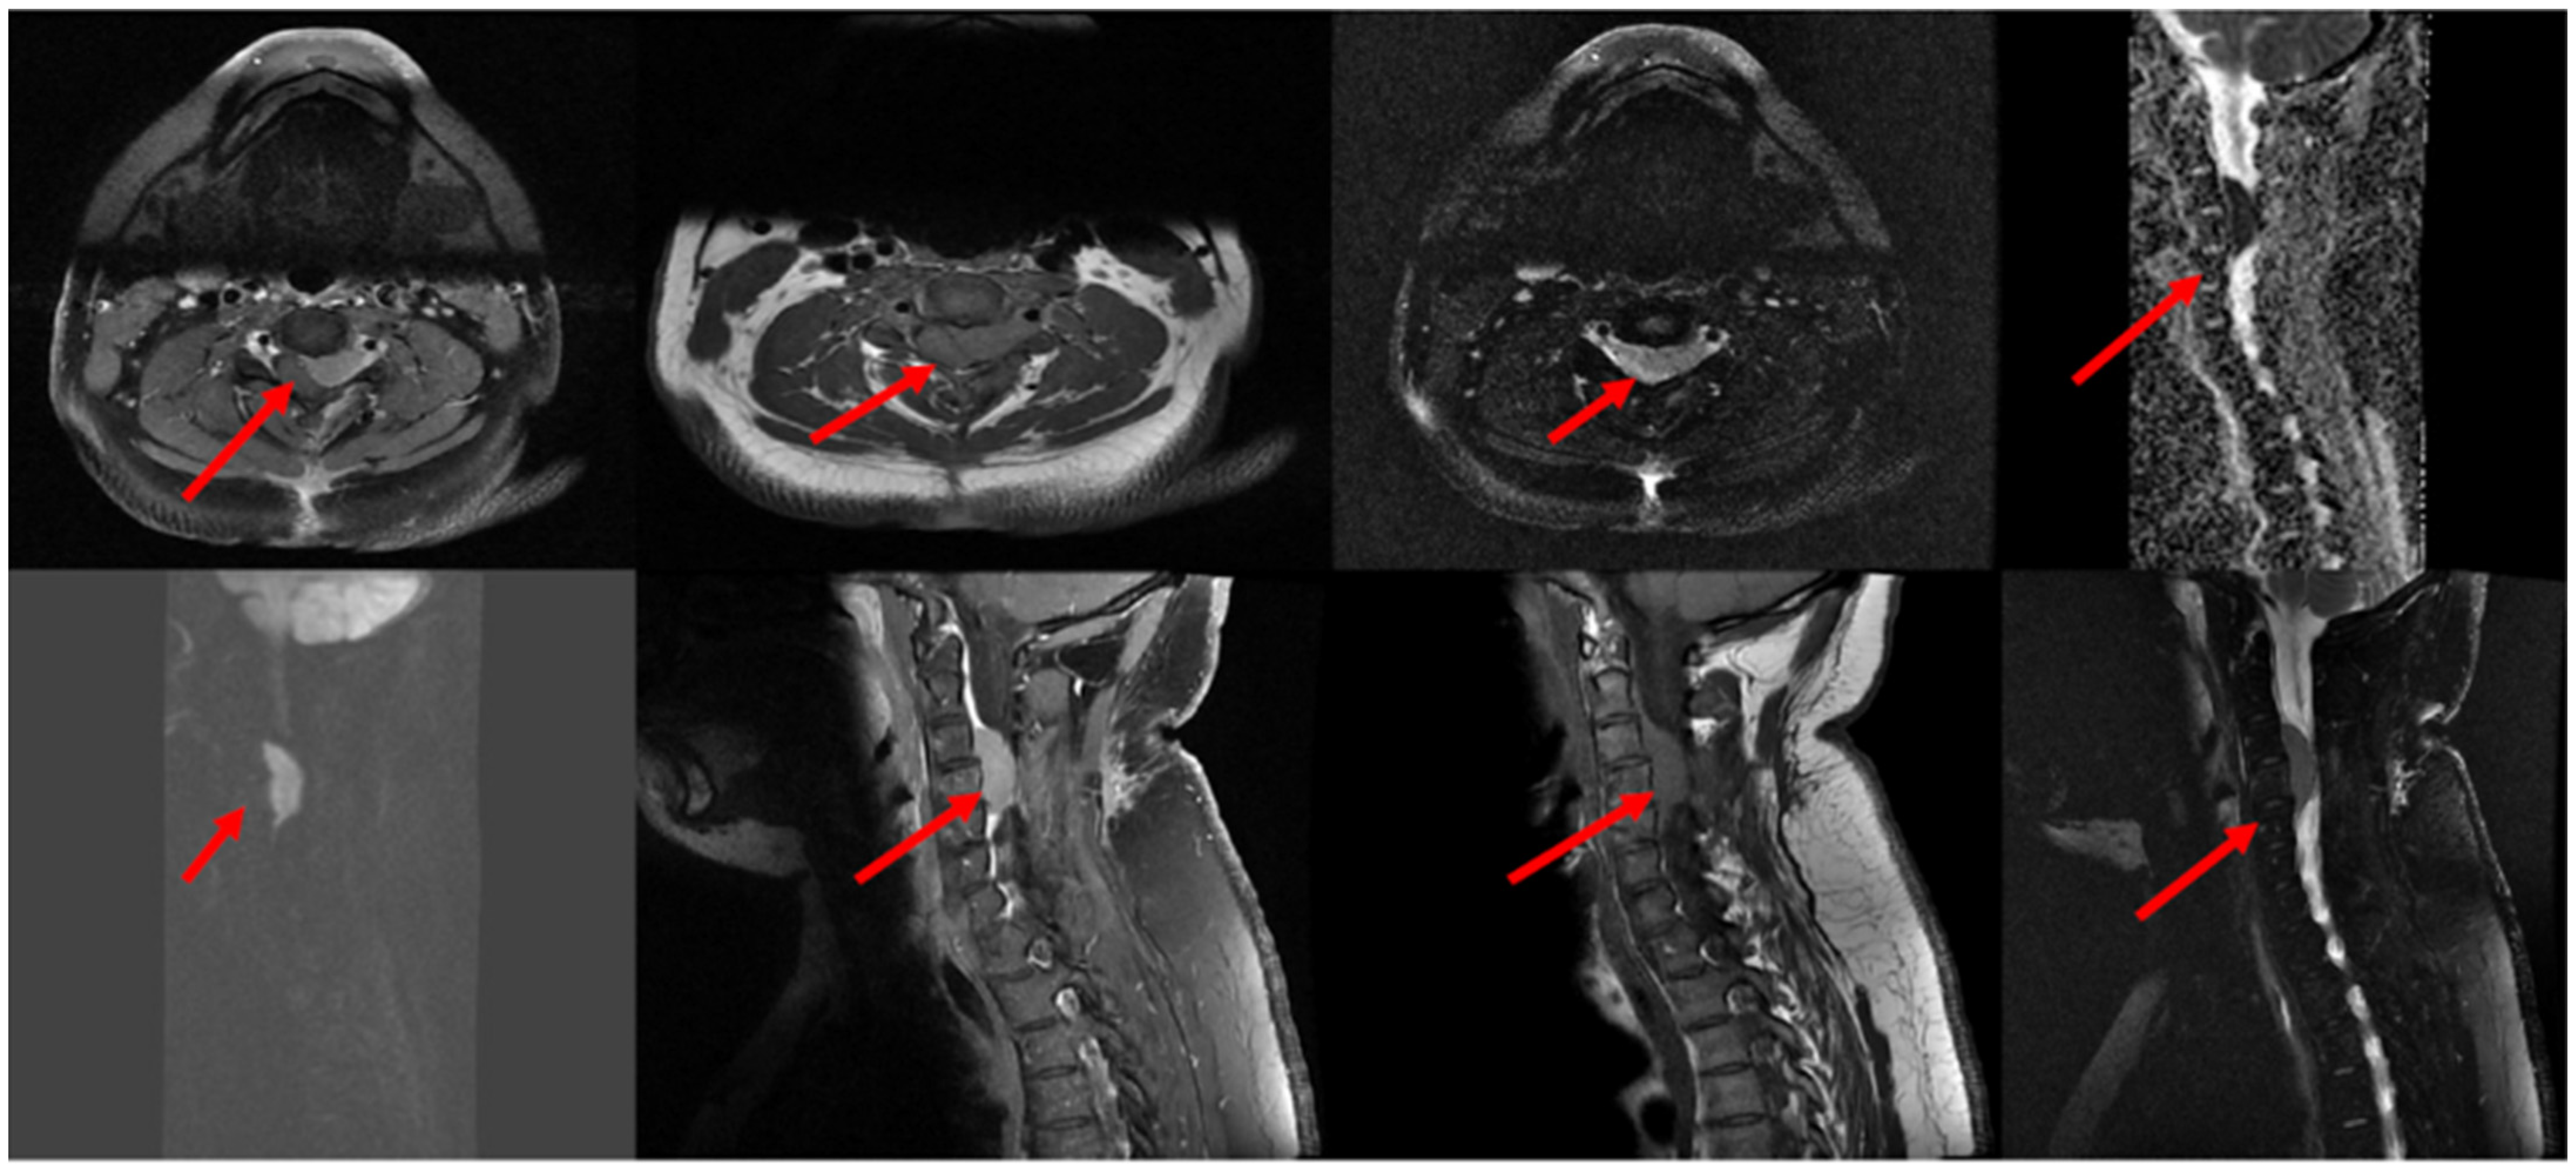

3. Case Description